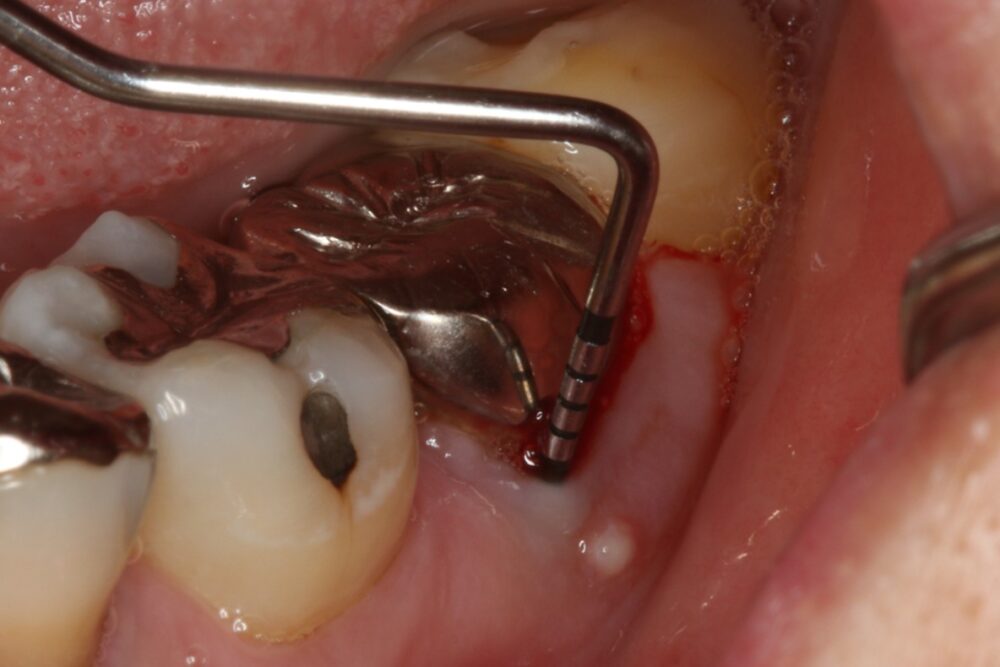

症例3

治療の流れ

親知らずの抜歯

| 医院の診断 | 歯根破折、慢性根尖性歯周炎 |

| ここがこだわりのポイント!☝ |

抜歯が必要になった際に余っている親知らずがあれば移植歯として利用することができます。 術前に撮影したCT画像から3Dプリンターを用いて親知らずのレプリカを作製することで、親知らずが乾燥することを防ぎ、成功率が上がるよう努力しています。 |